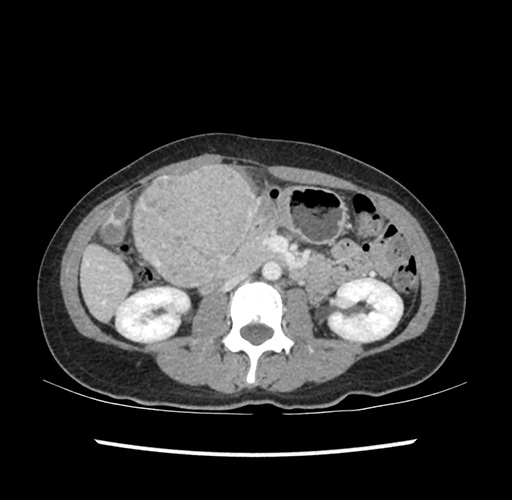

Imaging Analysis

Look through the patient's CT scan to identify any areas of concern for the necessary procedure.

Based on your CT findings, which issue(s) would give reason for "planned slowing down moment(s)" in this case?

Considering a standard left lateral sectionectomy procedure, what step(s) of the operation would you do differently in this case ?